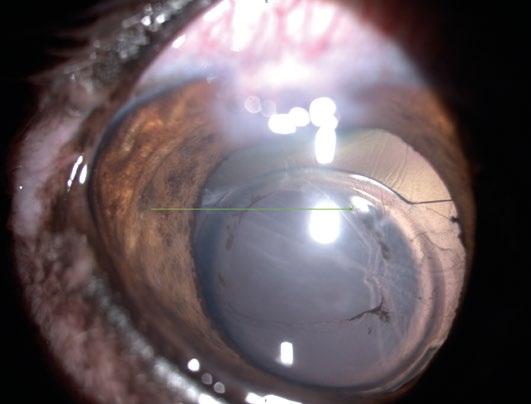

Tomografía de coherencia óptica